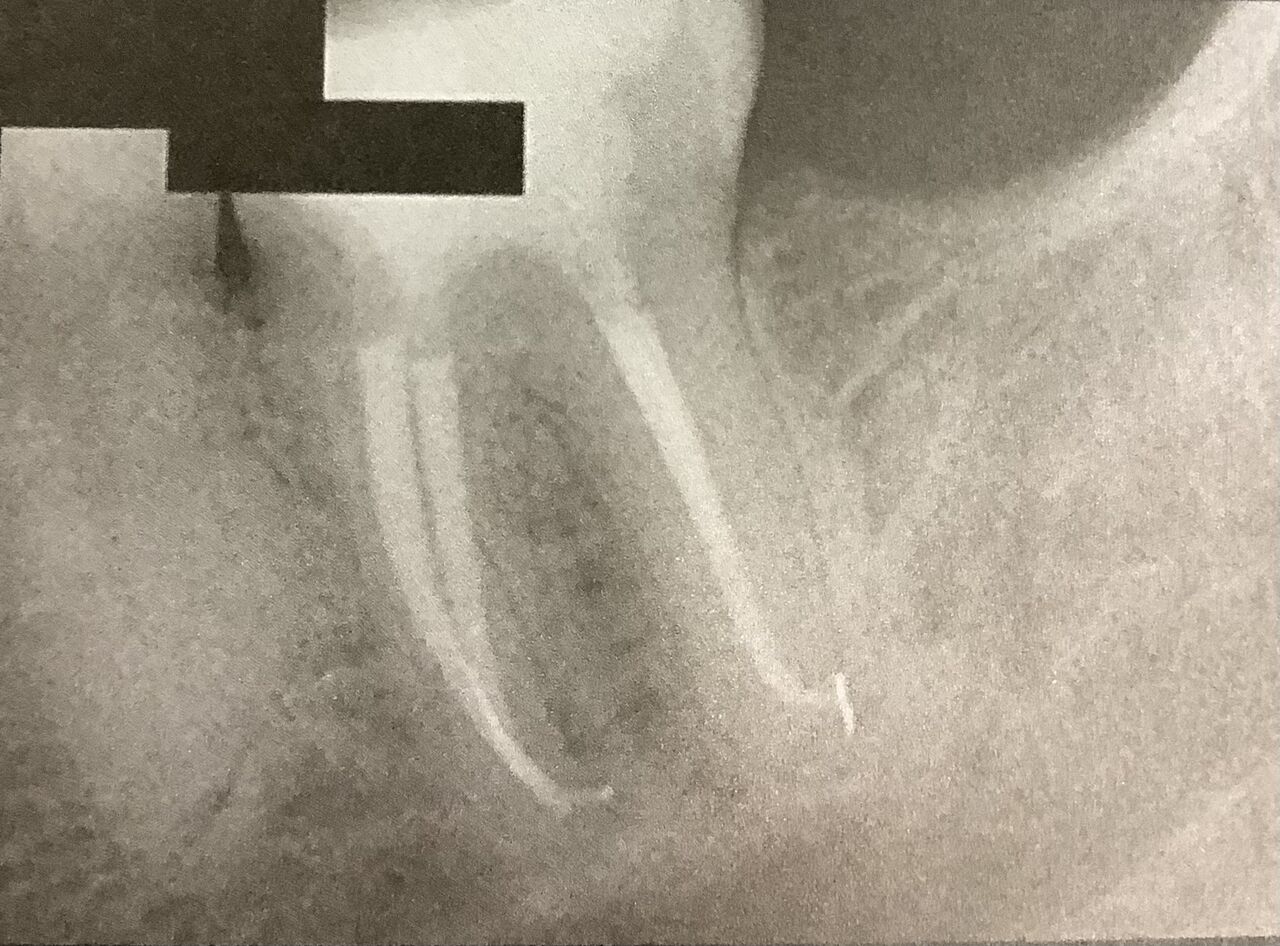

口の中には、痛みの原因となるようなものは見つかりません。

最近に根管治療をした6番も、押しても何ともありません。